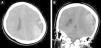

A 19-year-old female with sickle cell anemia (SCD) was referred to our hospital after two days of hospitalization at another hospital for a headache crisis. This headache crisis was due to a raised intracranial pressure; these symptoms were noted and included in her comprehensive list of symptoms. There was an acute drop in the hemoglobin and hematocrit levels. The cranial CT scan demonstrated a left fronto-parietal acute epidural hematoma (AEH) and a calvarial bone expansion, which was suggestive of medullary hematopoiesis. The patient underwent emergent craniotomy and evacuation of the hematoma. There were no abnormal findings intra-operatively apart from the AEH, except skull thickening and active petechial bleeding from the dural arteries. Repeated CT scan showed a complete evacuation of the hematoma. The possible underlying pathophysiological mechanisms were discussed. In addition to the factors mentioned in the relevant literature, any active petechial bleeding from the dural arteries on the separated surface of the dura from the skull could have contributed to the expanding of the AEH in our patient. Neurosurgeons and other health care providers should be aware of spontaneous AEH in patients with SCD.